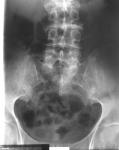

Alkaptonurija ili homogentizinska acidurija je redak kongenitalnidefekt u pretvaranju homogentizinske kiseline u acetosirćetnu kiselinu,pa se mokraćom izlučuju velike količine homogentizinske kiseline.